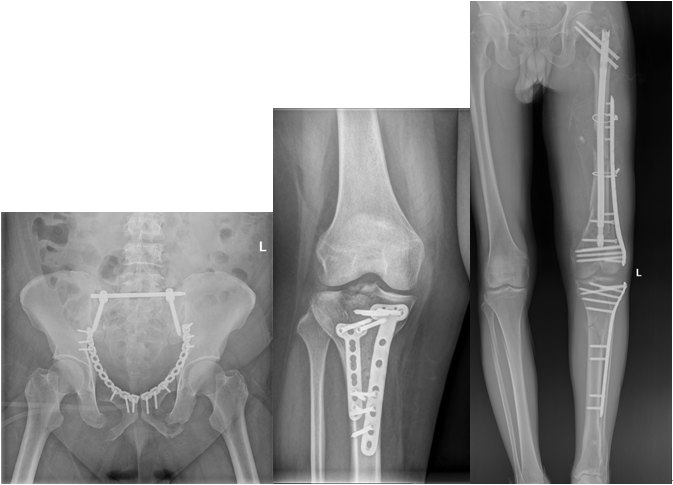

二、骨盆和肢體危重?fù)p傷骨折---應(yīng)急團(tuán)隊,挽救生命與功能

骨盆骨折和肢體嚴(yán)重?fù)p傷骨折多由嚴(yán)重暴力創(chuàng)傷引起,多合并有失血性休克與凝血病發(fā)生,若救治時機(jī)及方案不當(dāng),常可因大量失血和重度休克而引起死亡。創(chuàng)傷關(guān)節(jié)外科成立了多發(fā)傷應(yīng)急救治小組,通過協(xié)調(diào)重癥醫(yī)學(xué)科與相關(guān)科室,運用”損害控制”理念,一期采用骨盆帶、外固定架和控制性手術(shù)等技術(shù)手段搶救生命;二期采用微創(chuàng)內(nèi)固定、3D打印導(dǎo)板輔助空心釘固定、通道螺釘和各種肢體組織修復(fù)等高新技術(shù),重建骨盆與肢體的穩(wěn)定性,恢復(fù)肢體活動功能,在挽回生命的同時盡可能恢復(fù)患者肢體功能。

骨盆骨折內(nèi)固定術(shù)前、后